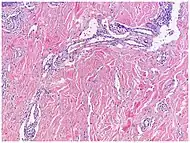

| Kaposi’s sarcoma in patch stage | The patch stage typically shows irregular proliferation of jagged vascular channels in the dermis below an integral epidermis. The so-called promontory sign is sometimes found in patch stage lesions and denotes vascular spaces surrounding pre-existing blood (see image).[23]

vessels |

|

|